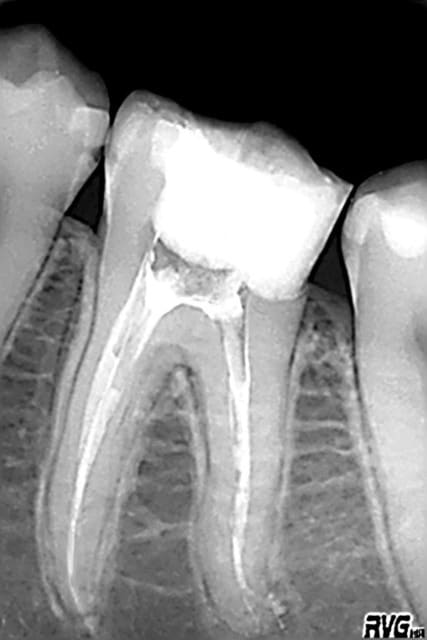

thermafil sans le laser à l'époque , cela marche aussi !

Thermafil t0zch4 - Eugenol